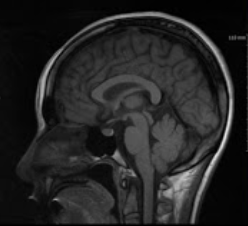

그리고 내년부터는 보장성강화를 위해 건강보험공단에서 복부 및 다른 부위에도 MRI 적용을 위해 제도 개선을 실시 중이라고 합니다.

모두들 정확한 시기에 검사를 받아 병을 키우는 일 없도록 하시길 바랍니다. 건강하세요.